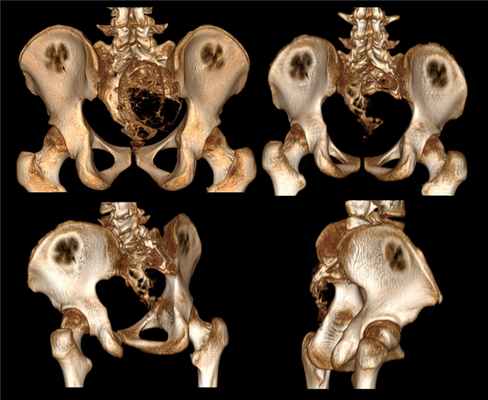

Хирургическое лечение проводилось у 78 пациентов в возрасте от 3 до 19 лет. Из них больных мужского пола — 32 (41 %), женского — 46 (59 %). По локализации: шейный отдел — 27 (35 %), грудной отдел — 15 (19 %), поясничный отдел — 21 (27 %), крестцовый отдел — 15 (19 %). В неврологическом статусе у 7 пациентов имелась неврологическая симптоматика связанная с формированием стеноза позвоночного канала новообразованием в виде нарастающего нижнего парапареза и верхнего парапареза в двух случаях за счёт аневризмальной кисты в шейном отделе позвоночника. При этом болевой синдром был выявлено в 62 случаях и в большинстве своём являлся причиной обращения к врачу для дальнейшего дообследования и постановки диагноза.

По данным КТ и МРТ исследований уровень жидкости определялся в 49 (63 %) случаях. По объёму поражения передней средней и задней опороной колонны пациенты распределены следующим образом (таблица).